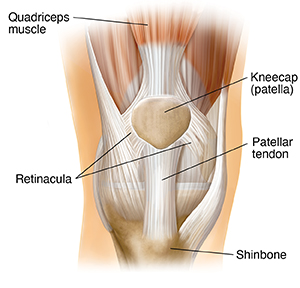

The kneecap (patella) is a small triangular bone that rests on the front of your knee. It is just one of the many parts that make up the knee joint. Some of the other parts are muscles, ligaments, and leg bones. The kneecap provides leverage for your muscles as they bend and straighten the leg. It also protects the knee joint.

Quadriceps muscles. These are at the front of the thigh. They help the kneecap slide against the thighbone. They also help to straighten the leg.

Kneecap. This allows the quadriceps muscles to work better as they tighten. The kneecap also protects the bones and tissues under it.

Retinacula. These are fibrous bands on the sides of the knee. They help hold the kneecap in place.

Patellar tendon. This is a fibrous cord that connects the kneecap to the shinbone.

Shinbone. This is the bone just below the knee. It is also called the tibia and is the second-longest bone of the body.